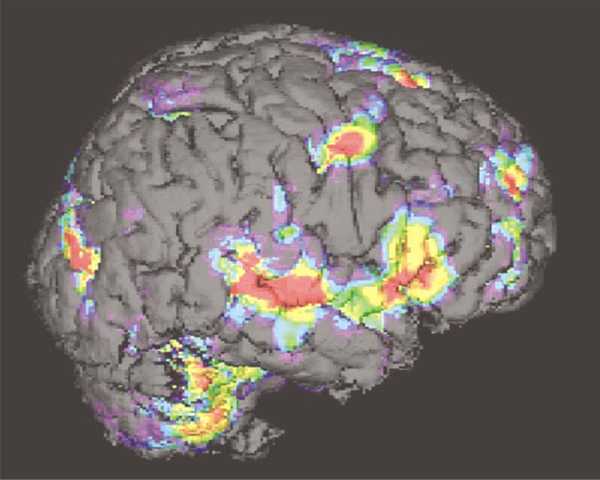

48_01LanguageMRI

language.html